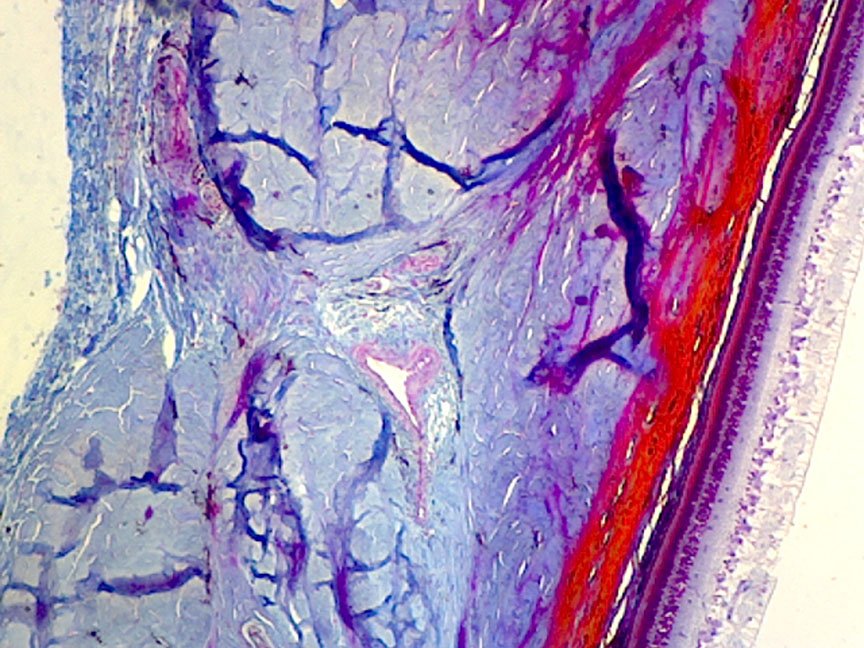

Solved Label the photomicrograph of the skin and its | Chegg.com Question: Label the photomicrograph of the skin and its accessory structures. Epidermis Sebaceous gland Hair follicle Duct of sebaceous gland Label the photomicrograph of the skin and its accessory structures. Solved Label the photomicrograph of the skin and its | Chegg.com Label the photomicrograph of the skin and its accessory structures. Epidermis Sebaceous gland Hair follicle Duct of sebaceous gland Label the photomicrograph of the skin and its accessory structures. Epidermis Sebaceous gland Hair follicle Duct of sebaceous gland ; Question: Label the photomicrograph of the skin and its accessory structures ...

Solved Label the photomicrograph of the skin and its 17.01.2020 · Biology. Biology questions and answers. Label the photomicrograph of the skin and its accessory structures. Sebaceous gland Duct of sebaceous gland Epidermis Hair follicle. Question: Label the …

Solved Label the photomicrograph of the skin and its | Chegg.com Question: Label the photomicrograph of the skin and its accessory structures. Sebaceous gland Duct of sebaceous gland Epidermis Hair follicle This problem has been solved! See the answer Show transcribed image text Expert Answer 100% (19 ratings)

PreLab03a Integument & Prelab03b Integument Histology - Quizlet Label the structures of the skin and subcutaneous tissues. Left side form top: ... stratum spinosum stratum basale. Categorize the appropriate structures or descriptions in the appropriate layer of skin that is highlighted in blue. Top layer: ... Label the photomicrograph of the skin and its accessory structures. epidermis hair follicle duct of ...